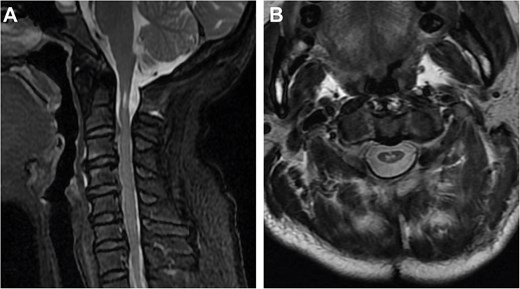

Cervical radiographs revealed hypoplasia of C1 but no evidence of atlantoaxial dislocation (Fig. 1). CT scans indicated bilateral bone abnormalities on the lateral sides of the posterior arch, particularly on the left side, with a midline cleft of the anterior arch (Fig. 2A). Three-dimensional reconstruction further demonstrated this abnormality (Fig. 2B–D). T2-weighted MRI revealed an intramedullary high signal at the C1 level, but no compression of the cord was observed (Fig. 3A and B). Cervical flexion-extension imaging indicated minor stenosis of the upper cervical spinal cord in the neck flexion position, but this alteration was not substantial (Fig. 3C–F). We considered that the high signal may be related to the repeated subtle activity of the posterior atlantoaxial arch in the past over a long period of time.

Sagittal and axial T2-weighted MRI of the cervical spine. (A, B) Supine neutral position. (C, D) Supine neck flexion position. (E, F) Supine neck extension position.